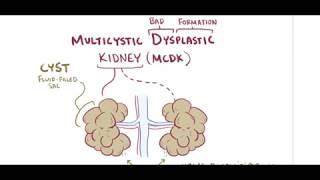

Mcdk

Mcdk

Mcdk. Смотреть видео: What Is Multicystic Dysplastic Kidney MCDK Symbiosis Speciality Hospital, MCDK As A Cause Of ANHYDRAMNIOS In 21wks ALIVE FETUS, Multi Cystic Dysplastic Kidneys Explained Animated Patient Info, Having A Baby With A Multicystic Dysplastic Kidney One Born Every Minute.